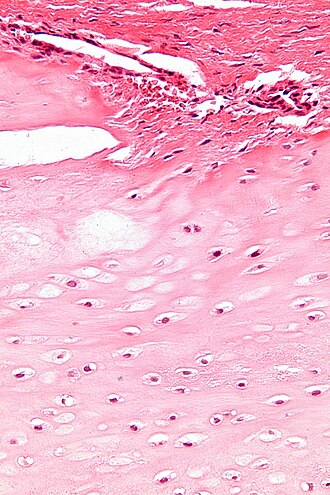

Template:Px Enchondroma. H&E stain. | |

Microscopic

Features:

- Cytologically benign cells is spaced nests.

- Should not extending into surrounding soft tissue.

DDx:

- Low-grade chondrosarcoma - should be considered, correlation with radiology essential.

The sections show spaced small cells in a pale matrix with a light-blue tinge. No nuclear atypia is appreciated. No mitotic activity is apparent. Degenerative changes are seen focally.

A small focus of cholesterol clefts with giant cells is present. Benign bone, bone marrow and skeletal muscle are present.